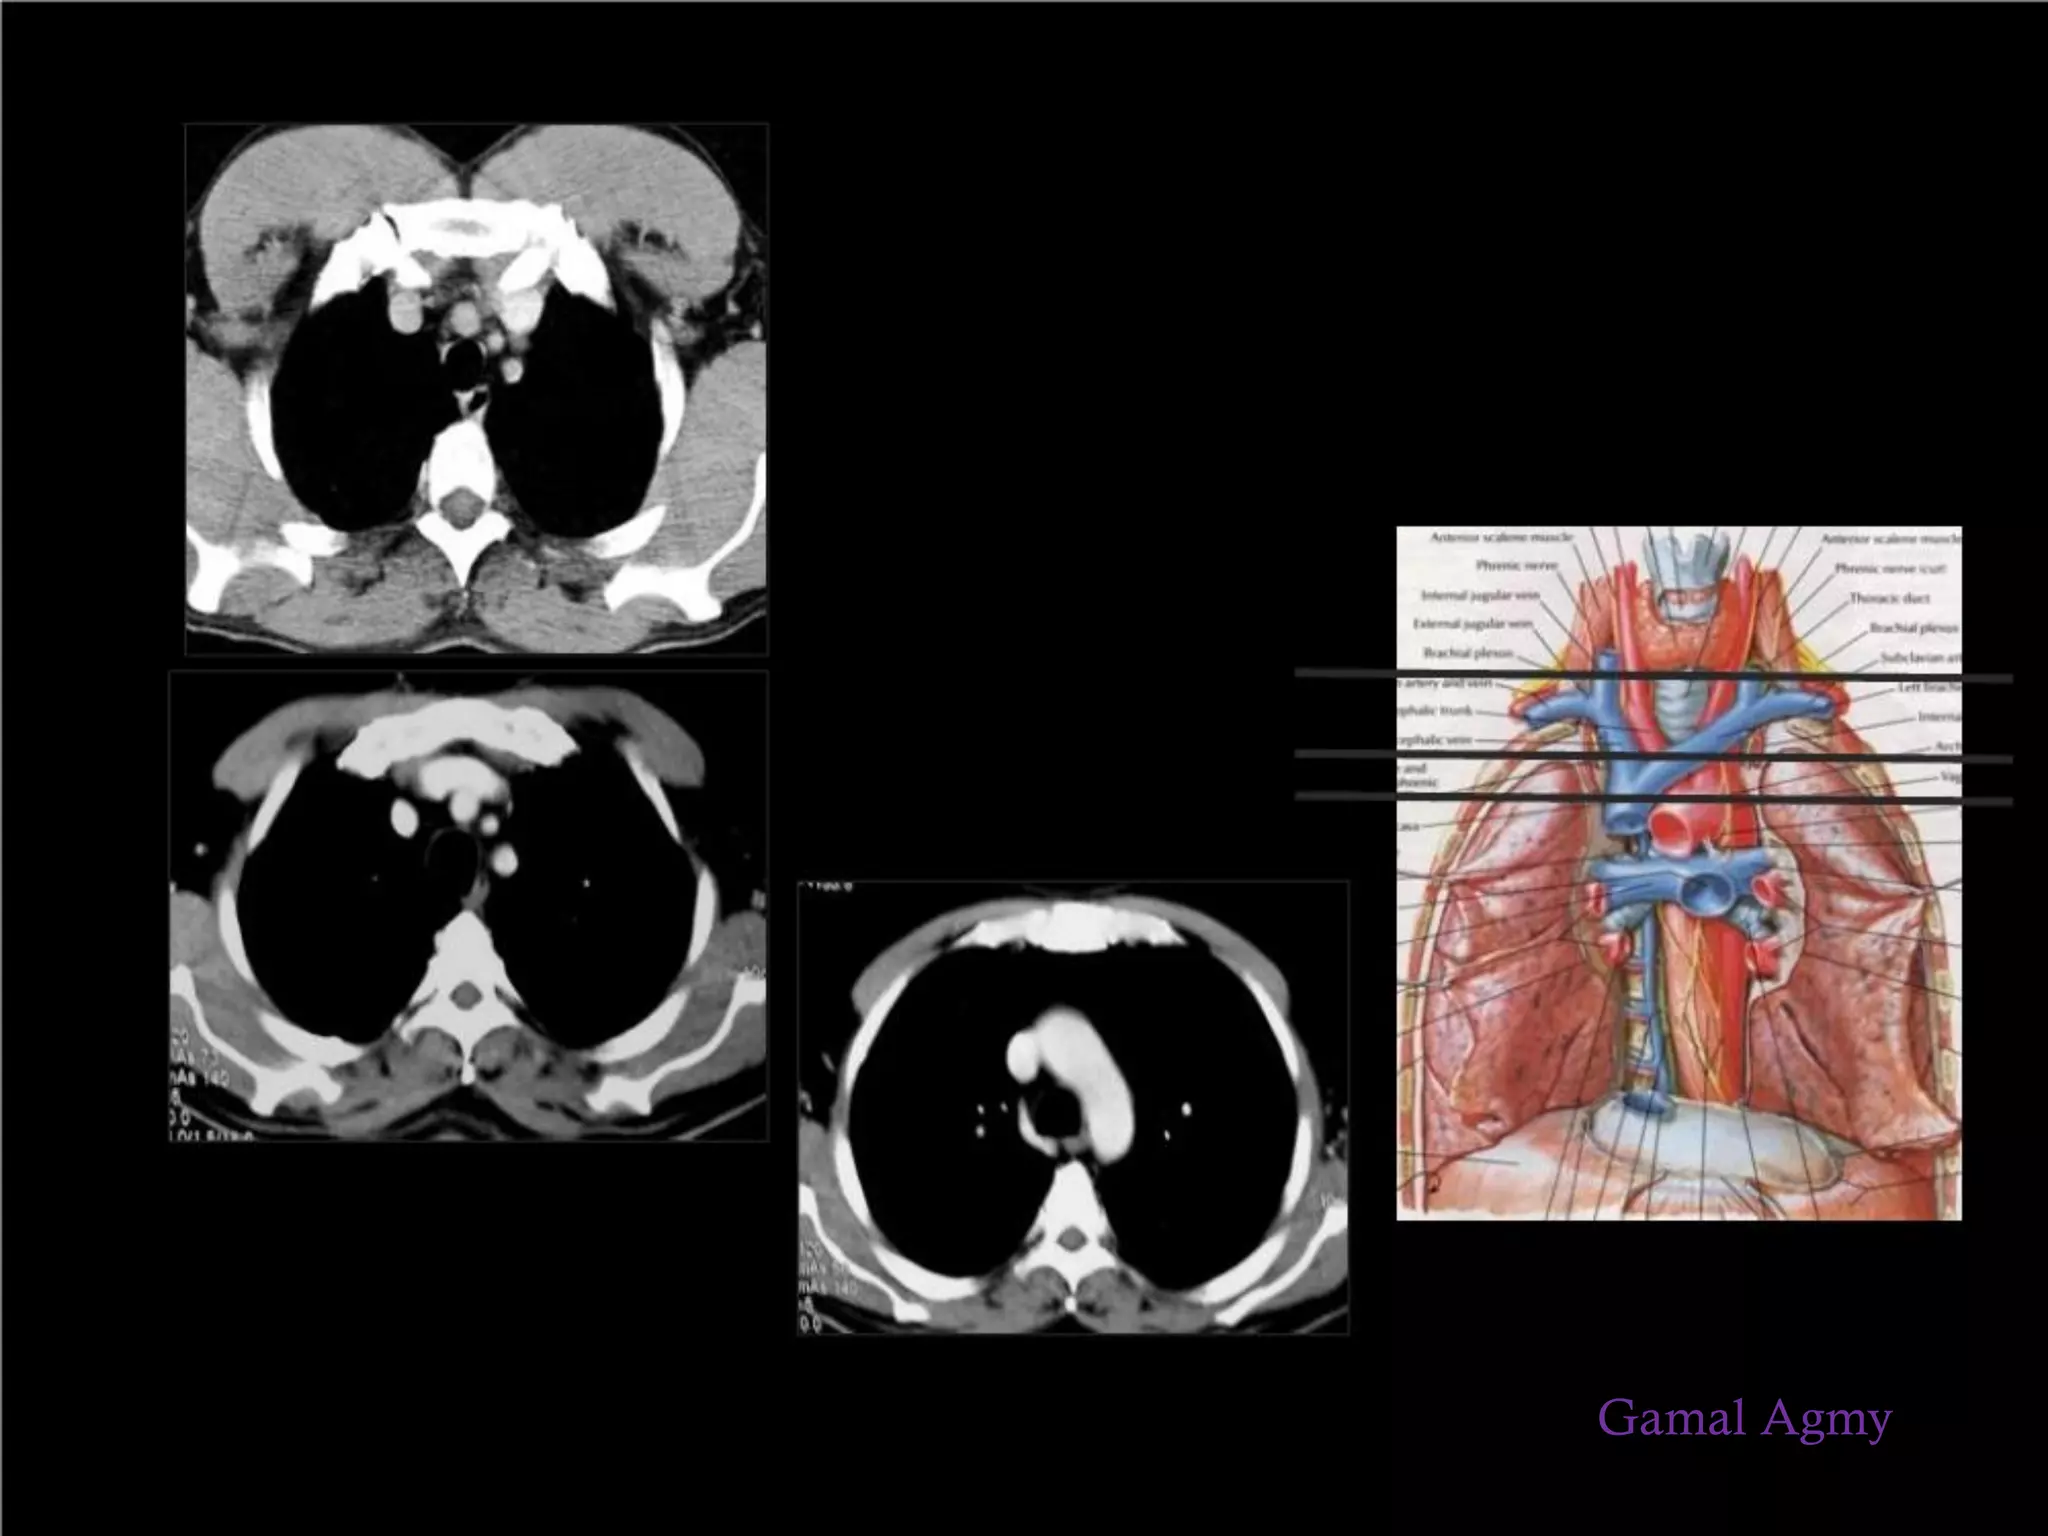

Axial CT of Lymph Nodes

Scroll through the images on the left.

1-Sternal notch nodes are just seen at this level and

above this level

2-Upper Paratracheal: below clavicles and on the

right above the intersection of caudal margin of

innominate (left brachiocephalic) vein with the

trachea and on the left above the aortic arch.

3-Pre-vascular and Retrotracheal : anterior to the

vessels (3A) or prevertebral (3P)

4-Lower Paratracheal : below upper margin of

aortic arch down to level of main bronchus

5-Subaortic (A-P window): nodes lateral to

ligamentum arteriosum or lateral to aorta or left

pulmonary artery

6-Para-aortic: nodes lying anterior and lateral to the

ascending aorta and the aortic arch beneath the

upper margin of the aortic arch

7-Subcarinal

8-Paraesophageal (below carina)

9-Pulmonary Ligament: nodes lying within the

pulmonary ligament.

10--14: nodes are all N1 nodes